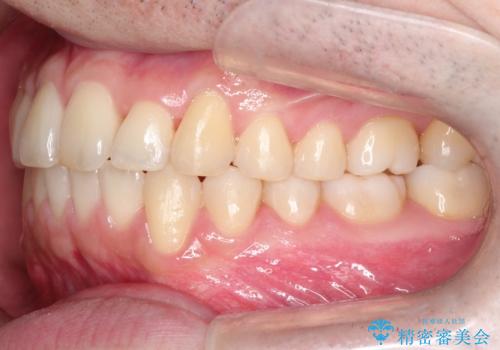

治療期間も短く大変満足していただきました。